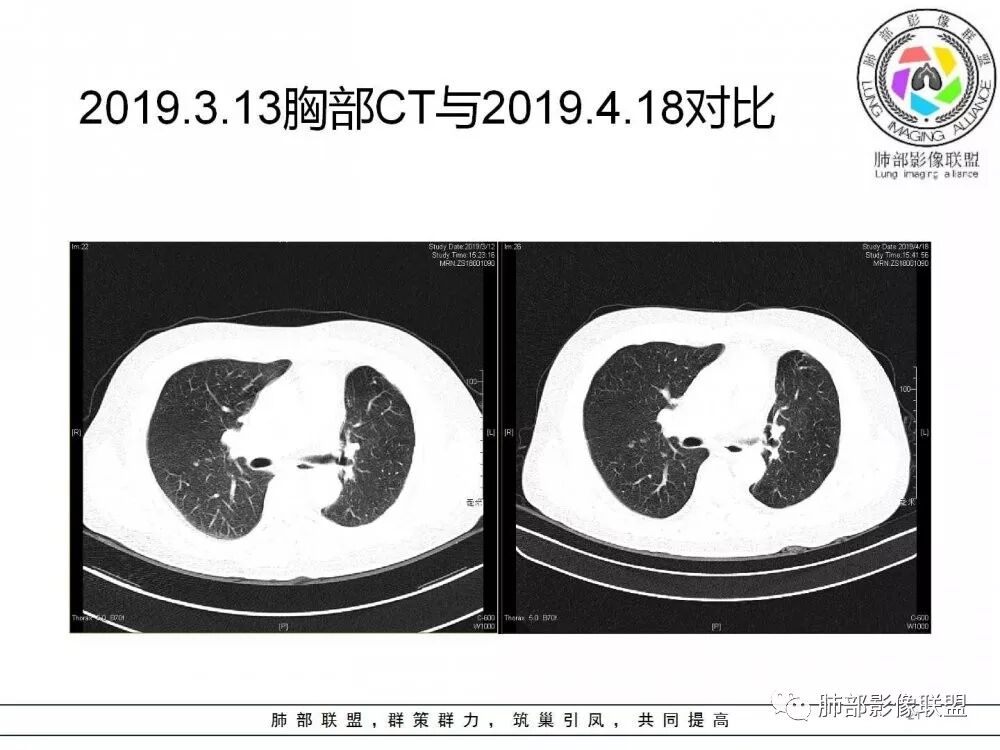

肺部病灶从2月份就开始有了,应该最早说是1月7号就有了,到3月13号稍微增大一点,到后面几乎就没变化了,到5月份好像稍微大一些,炎性肯定是炎性,就是这个炎性是到底什么病变呢?其实本没变化,它特点一个是在叶裂上,跟血管关系密切,但是病灶边缘稍收缩,病灶这么没有太大变化,我还是支持炎性病变。

确实当时病人来了考虑转移可能,就测了基因,上了靶向药,两月变化不大

因为这个长轴似乎跟支气管走行一致的,其实治疗效果不是很理想,我先把性质定为炎性。因为这个病灶它沿着血管支气管走行的方向,大家都考虑隐球菌,这么久病灶无明显变化,它跟血管束关系很密切。我犹豫就在此,到底是IgG4还是隐球,大方向是炎性,不符合的就是也在激素治疗。

19年3月份才吃靶向药